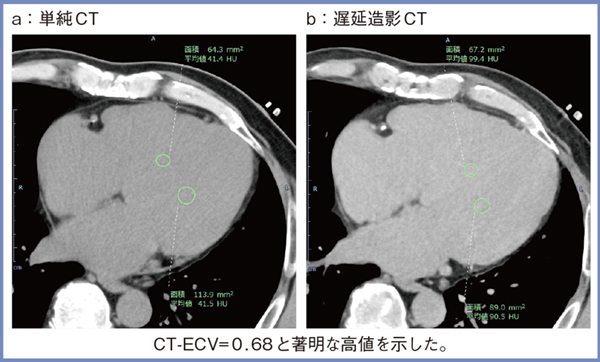

心アミロイドーシスの画像診断には,MRI,CT,骨シンチグラフィが用いられる。症例3は,冠動脈疾患の精査目的で冠動脈CTを行った症例で,CT-ECVが診断のきっかけとなった一例である。CT-ECVの値は正常値(0.30未満)の約2倍に当たる0.68という高値を示し(図4),MRI-ECVでも0.66と,ほぼ同等の値を示した。本症例は,ピロリン酸シンチグラフィや心筋生検でもアミロイド陽性となり,野生型のATTR型心アミロイドーシスと診断された。

図4 症例3:冠動脈疾患の精査目的で冠動脈CTを施行した症例